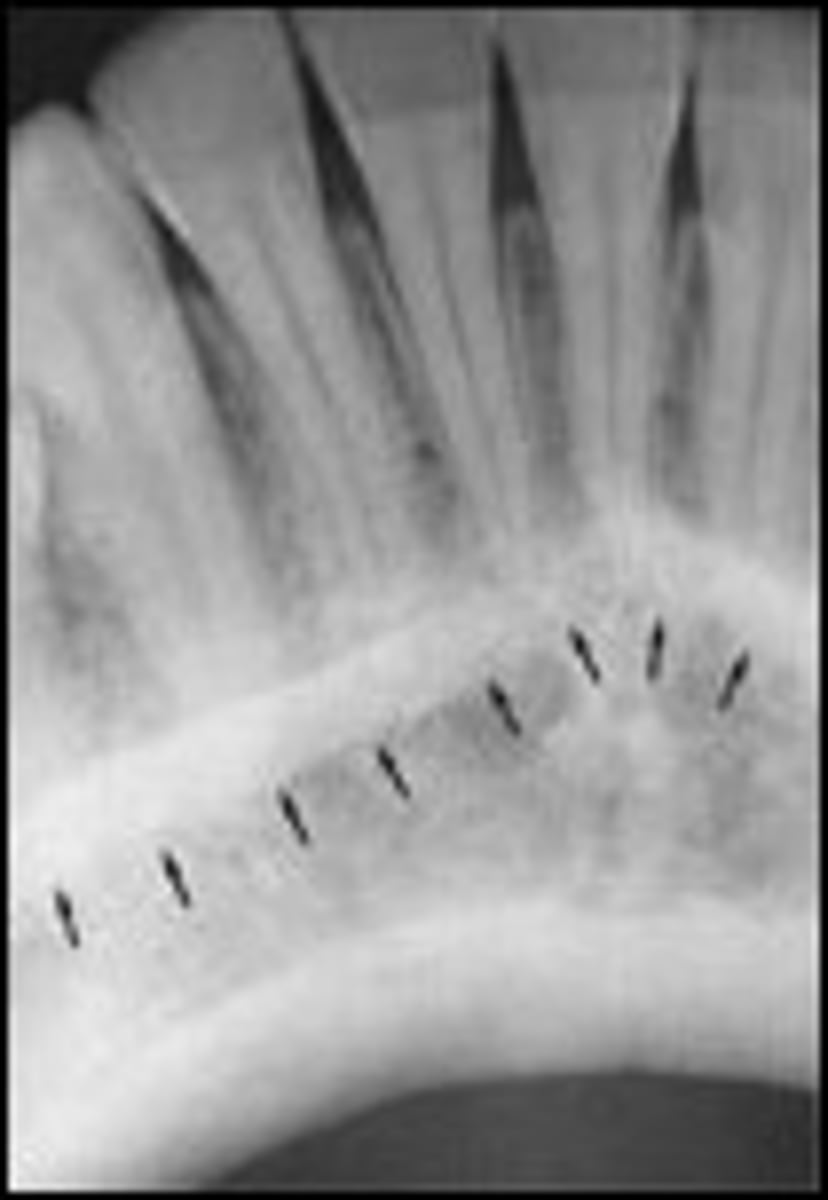

external oblique ridge

dense white line distal to the last molar and moving across root of molars

internal oblique ridge

located below the external oblique ridge

less dense

ridge of bone that extends across roots